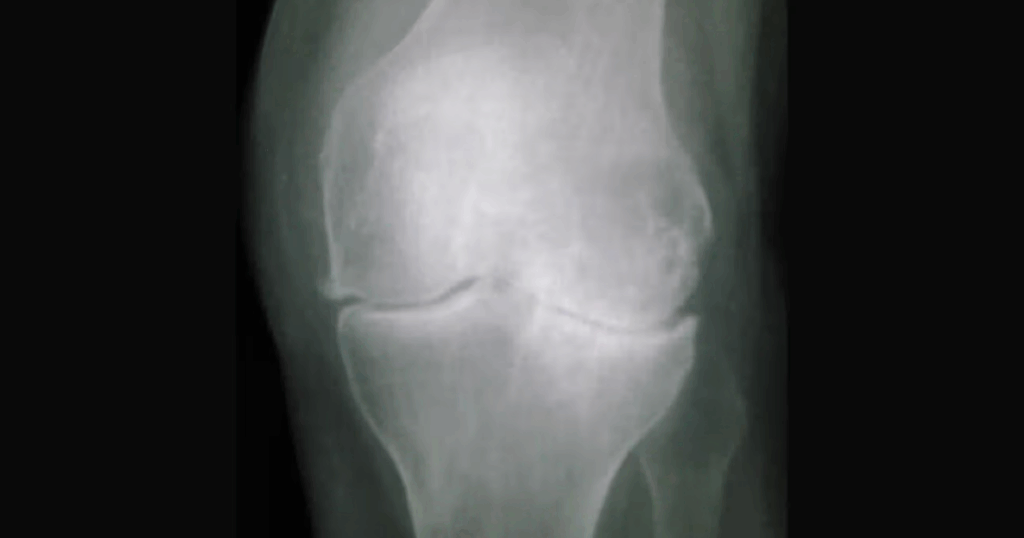

Trong chẩn đoán thoái hóa khớp gối, thăm khám lâm sàng là nền tảng nhưng chưa đủ để xác định toàn diện tình trạng tổn thương. Chẩn đoán hình ảnh đóng vai trò bổ sung quan trọng, giúp bác sĩ nhận diện chính xác các thay đổi cấu trúc ở sụn khớp, xương dưới sụn và phần mềm quanh khớp. X-quang thường là phương tiện đầu tiên được chỉ định vì dễ thực hiện, chi phí thấp và cho thấy những đặc điểm kinh điển của thoái hóa như hẹp khe khớp hay hình thành gai xương. Tuy nhiên, ở những trường hợp cần đánh giá chi tiết hơn, cộng hưởng từ (MRI) lại mang lại nhiều thông tin giá trị về sụn khớp, sụn chêm, dây chằng và màng hoạt dịch – những cấu trúc không thể quan sát bằng X-quang.